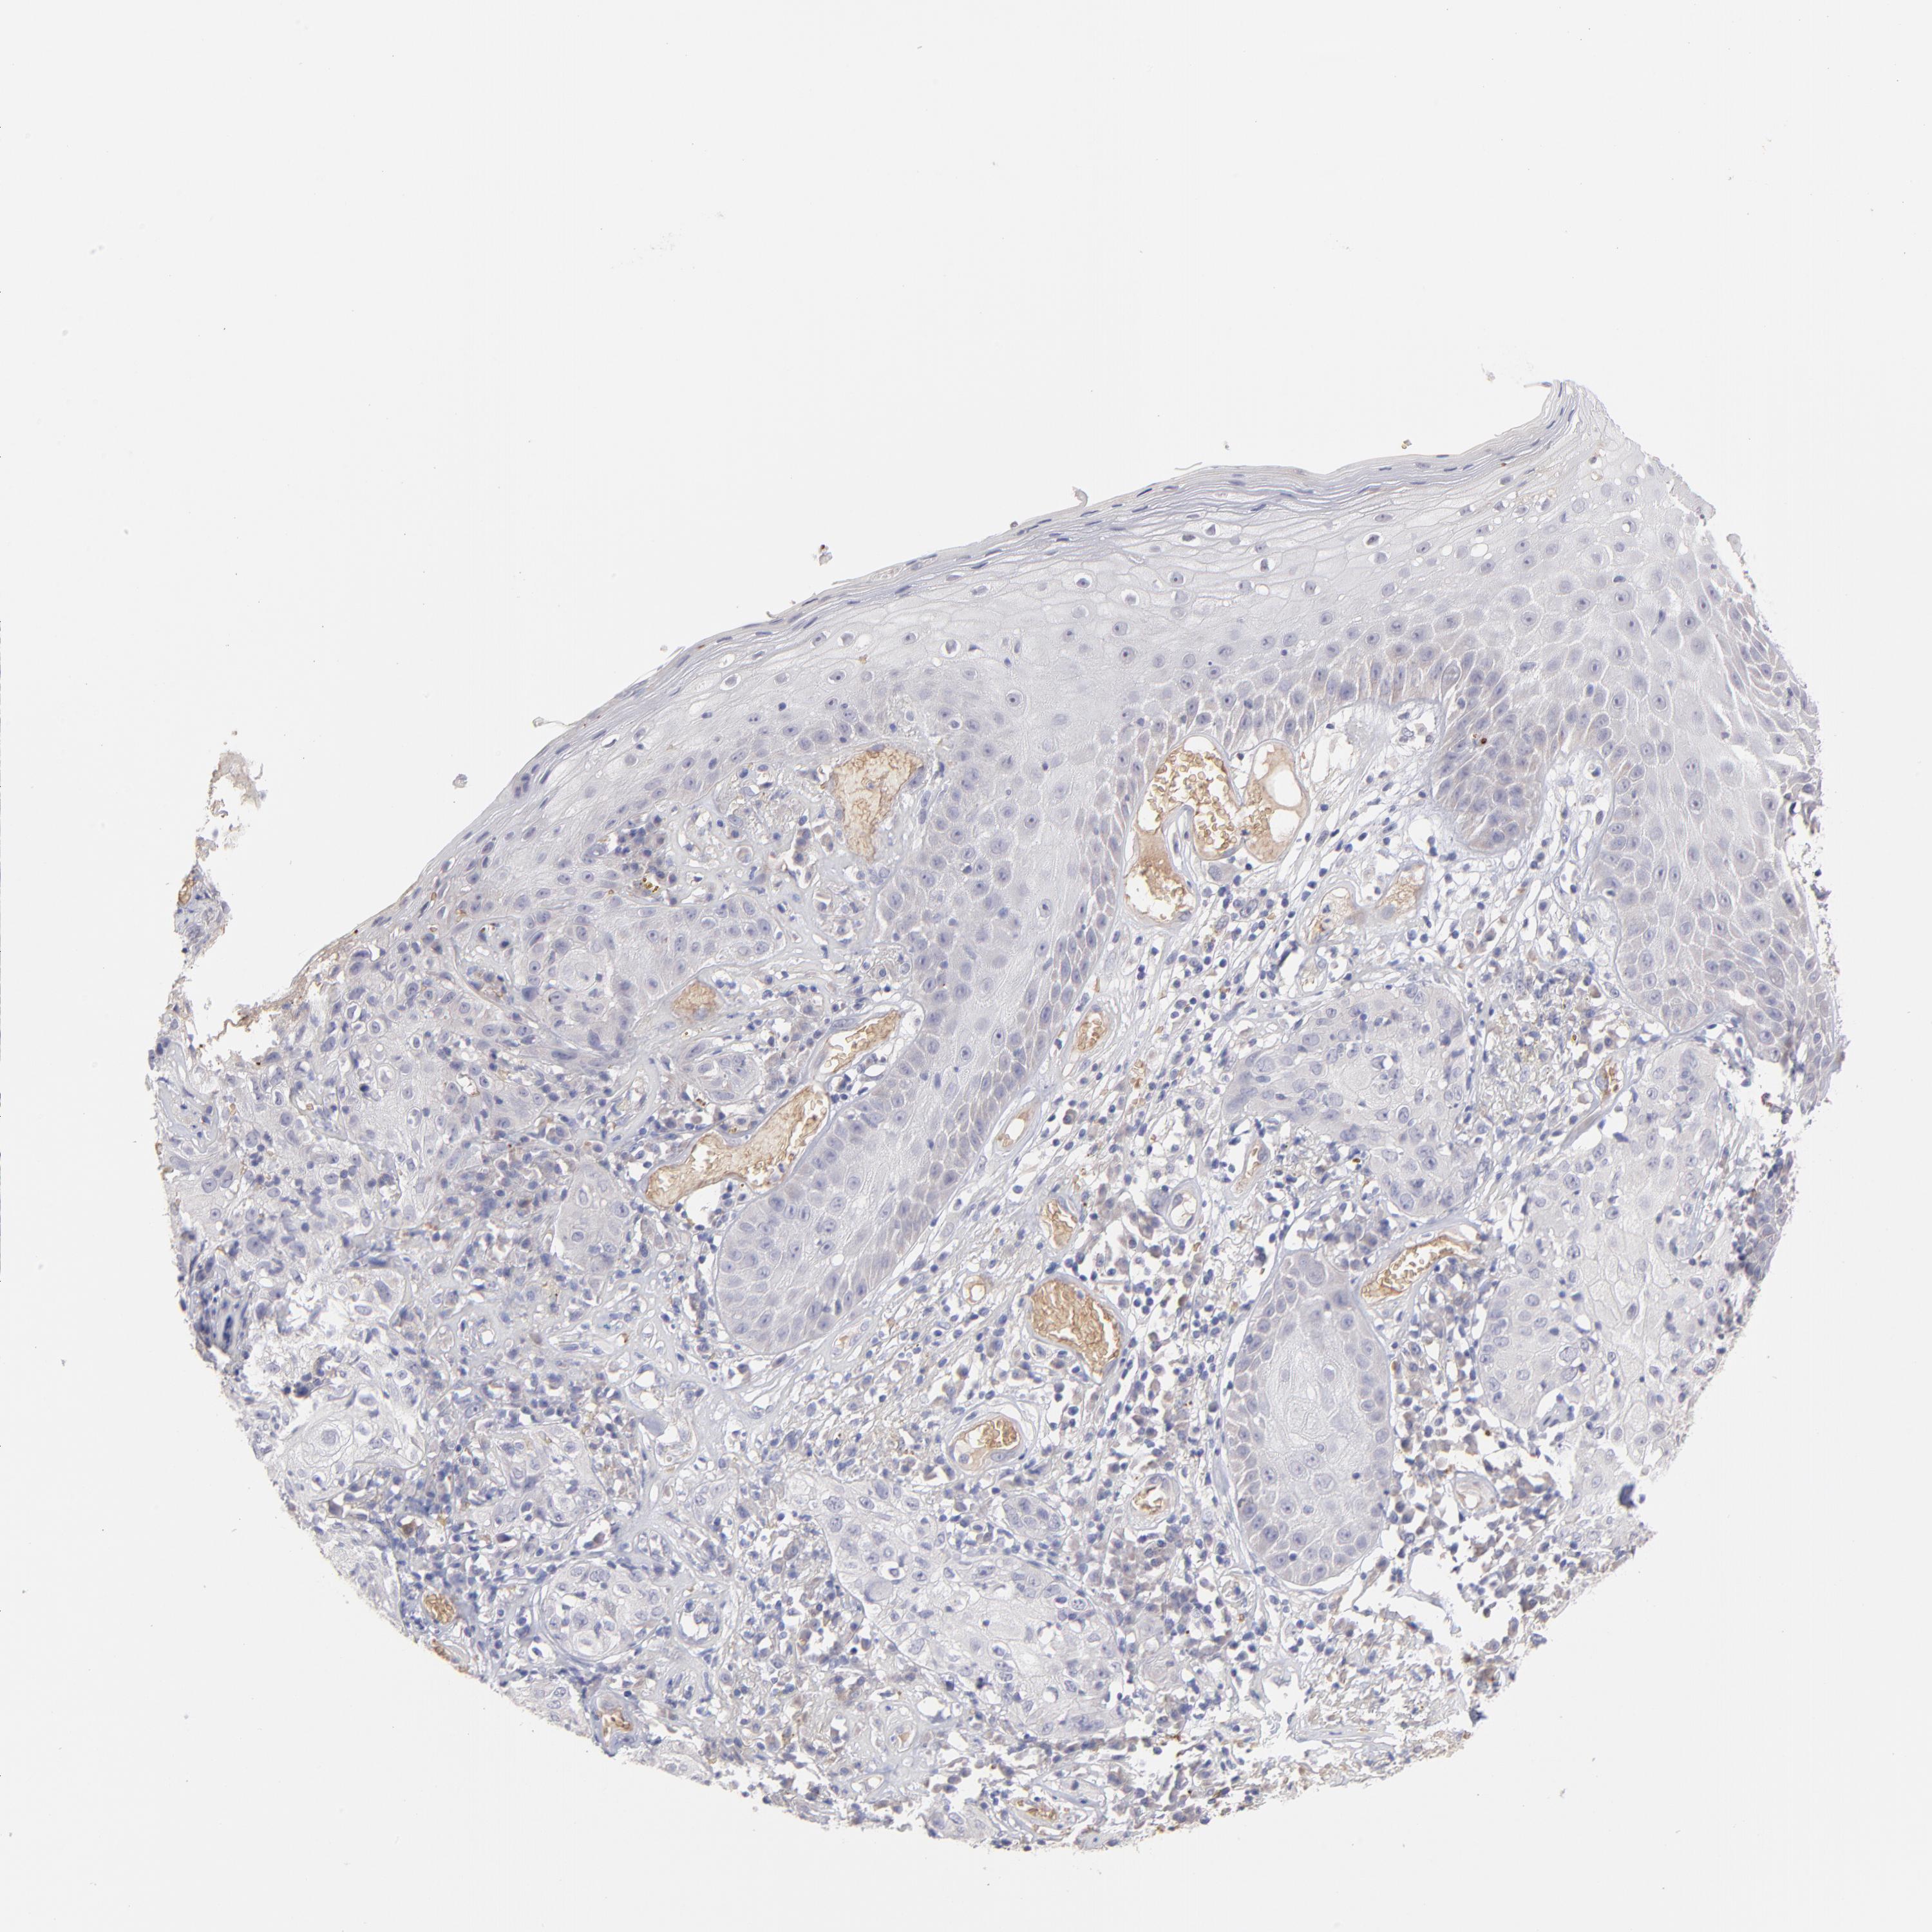

Basal cell and squamous cell cancer

SKIN CANCER - Protein expressioni

A mouse-over function shows sample information and annotation data. Click on an image to view it in a full screen mode. Samples can be filtered based on level of antibody staining by selecting one or several of the following categories: high, medium, low and not detected. The assay and annotation is described here.

Antibody stainingi

Antibody staining in the annotated cell types in the current human tissue is reported as not detected, low, medium, or high, based on conventional immunohistochemistry profiling in selected tissues. This score is based on the combination of the staining intensity and fraction of stained cells.

Each image is clickable and will lead to virtual microscopy that enables deeper exploration of all samples and also displays staining intensity scores, fraction scores and subcellular localization as well as patient and tissue information for each sample.

Antibody HPA003827

Antibody HPA052139

Staining

High

Medium

Low

Not detected

Intensity

Strong

Moderate

Weak

Negative

Quantity

>75%

75%-25%

<25%

None

Location

Nuclear

Cytoplasmic/membranous

Cytoplasmic/membranous,nuclear

Squamous cell carcinoma, NOS

Basal cell carcinoma